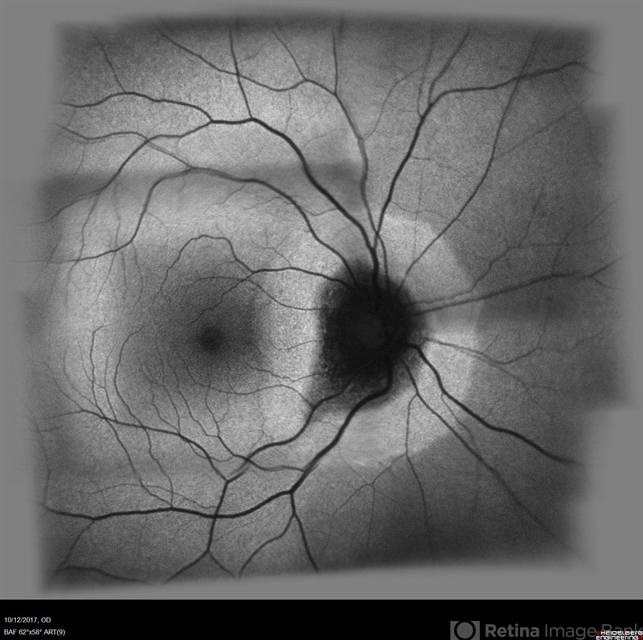

- acute zonal occult outer retinopathy (AZOOR)

- fundus autofluorescence OD showing peripapillary hypoautofluorescence surrounded by an area of hyperautofluorescence with well demarcated margins suggestive of AZOOR.